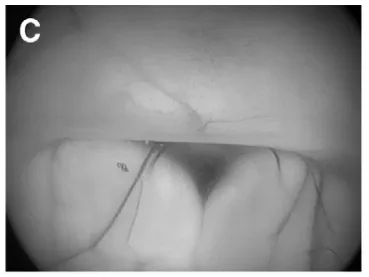

(C)第三脑室底,可见乳头体。